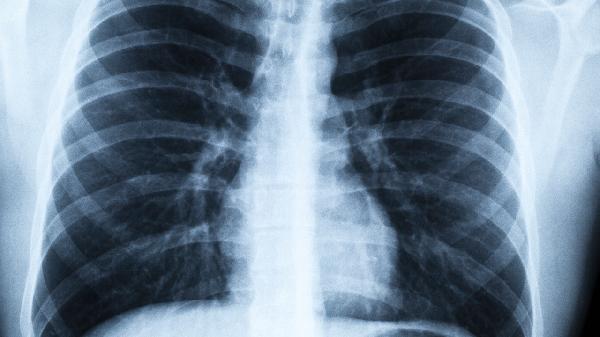

肺病加重之前,喉咙有信号?提醒:若出现4个异常,或是癌症来袭

肺部的健康警.报往往最先在喉咙拉响!很多人以为咳嗽几声只是小感冒,殊不知这些细微变化可能是身体在拼命发送求.救信号。当肺部开始"抗议"时,喉咙会变成最敏感的警.报器。

出现上述症状不要拖,最佳排查时间是症状出现后的1个月内。医生可能会建议做喉镜、胸部CT等检查。记住,早期发现的肺部问题,干预效果会好很多。